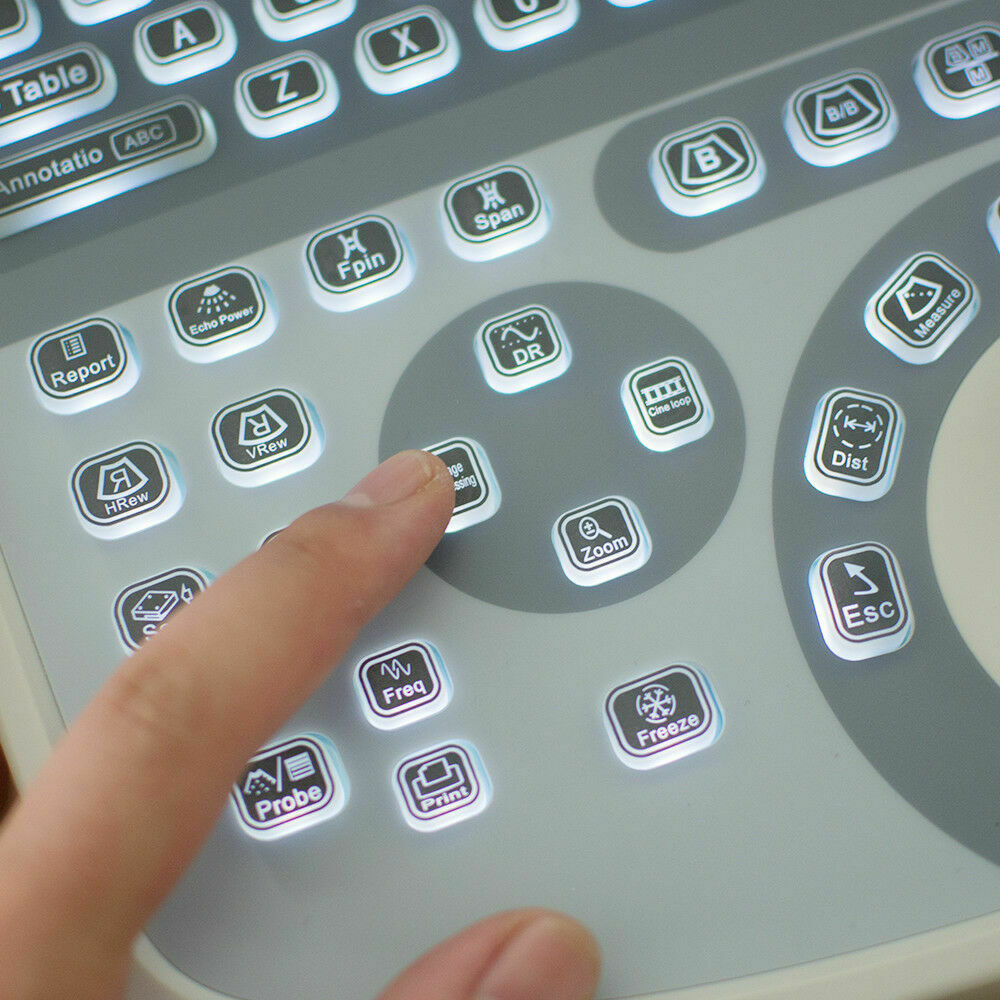

Moreover, the New Portable Notebook Digital Laptop Machine Ultrasound Scanner features an intuitive user interface that simplifies the ultrasound process. Medical professionals can easily navigate through the software, customize settings according to their needs, and save images for later review. This level of user-friendliness ensures that both experienced practitioners and those new to ultrasound technology can effectively operate the device, improving patient care outcomes.